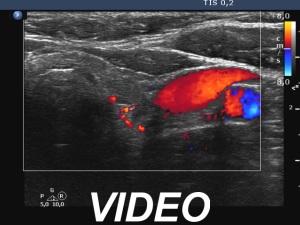

Ultrasonography. The right lobe was substantially enlarged and hypoechoic. It had macrocalcifications. The issue was whether the lobe was composed of a large nodule or only diffuse enlargement was present. The left lobe was much smaller. This lobe was also hypoechoic but to a lesser extent as was the right lobe. The vascularity was increased in the right while decreased in the left lobe.

The issue was whether the lobe was composed of a large nodule or only diffuse enlargement was present. On some still images, it seemed evident that there was a nodule. But we should never forget, that the reality is much more represented by videos. When we stop the continuous scan significantly affects what we see in a still image, which can therefore very easily be misleading. In the video, I highlighted those features on which we could decide considering only the ultrasound presentation that this very likely a nodule.

- The most decisive fact was the palpation that this was a nodule.